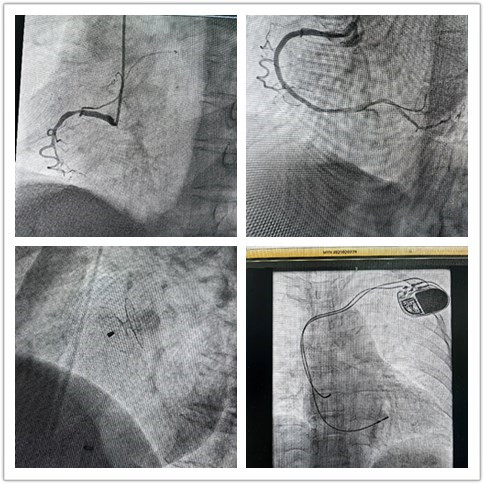

“组团式”帮扶队员—心内科邓纪钊,立即组织指导多学科团队开通胸痛绿色通道,有条不紊进行急诊术前相关检查,诊断为急性下壁心肌梗死。绕行病房,直达介入手术室,仅用32分钟顺利开通血管,患者转危为安,预后良好。

胸痛中心专科联盟平台进行胸痛患者的会诊、手术指导、学科共建等,制定了符合镇安县医院实际情况的胸痛患者诊疗流程,将急性心肌梗死药物溶栓治疗前移到急诊科。同时加强胸痛患者接诊—分诊分级—处理—转运—交接流程管理,多次进行院内及县域医共体内胸痛知识培训,举办“心梗拨打120,胸痛中心快救命”大型主题义诊宣教活动,旨在提高整个县域内百姓健康意识。通过追溯反馈、质控分析规范流程等机制,有效降低胸痛患者的致死和致残。

用“心”医治,点亮生命,是医者的初心使命。借力“组团式”帮扶,镇安县医院心内科救治能力和水平不断提高,业务范围不断扩展,先后完成多例卵圆孔未闭封堵、永久性心脏起搏器植入、心律失常射频消融术等。县医院从2022年3月组建介入科至今,截至发稿,冠脉介入手术已逾1000例,急诊冠脉内介入治疗手术已过百例,无1例手术相关医疗事件发生。这是镇安县医院发展史上的里程碑,也是前行的新起点。相信在三级片